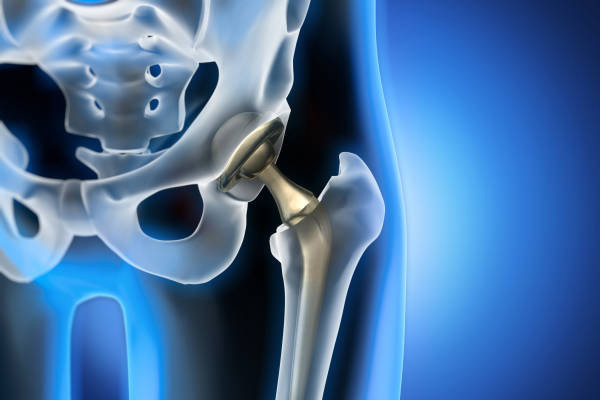

Total Hip Replacements